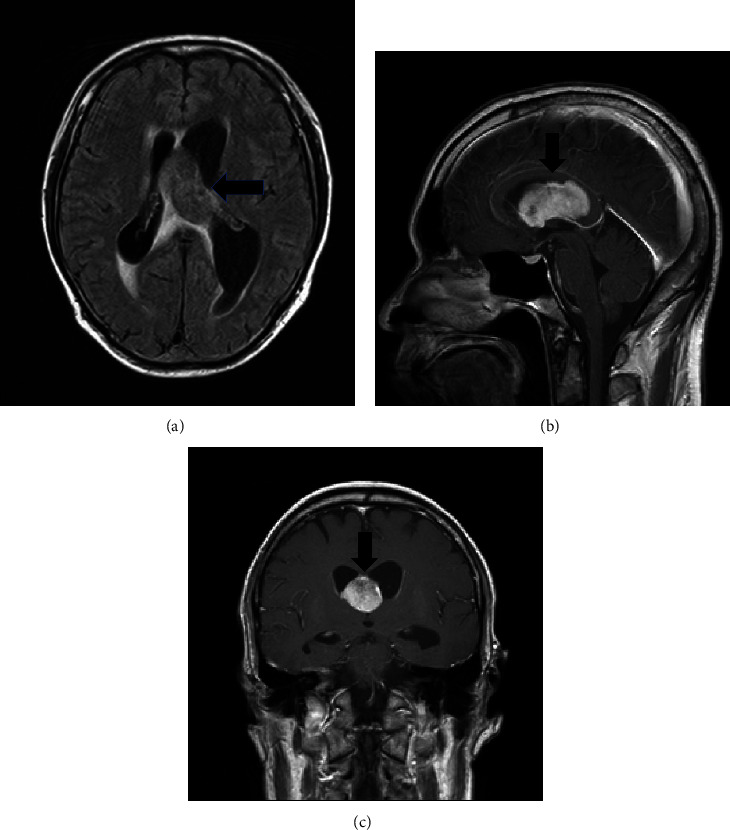

尽管采用了抗逆转录病毒疗法(ART),人类免疫缺陷病毒(HIV)相关淋巴瘤仍有很高的致死风险。虽然中度或高度B细胞淋巴瘤很常见,但无细胞大细胞淋巴瘤(ALCL)却很罕见,而且很少累及中枢神经系统(CNS)。在此,我们介绍了一例与艾滋病毒相关的孤立性中枢神经系统受累的 ALCL,该病例发生在终止抗逆转录病毒疗法后,当时正在接受布伦妥昔单抗维多汀(BV)治疗--BV 不能透过血脑屏障。中枢神经系统复发时,患者的 CD4 细胞数为 9 cells/mm3。这是首例HIV相关ALCL中枢神经系统复发的报告。考虑到中枢神经系统复发的高风险,我们建议在HIV相关ALCL病例中启动中枢神经系统预防措施,尤其是接受BV等中枢神经系统渗透性药物治疗的患者。

Human immunodeficiency virus (HIV)-associated lymphoma poses a high mortality risk despite antiretroviral therapy (ART). Although intermediate- or high-grade B-cell lymphomas are common, anaplastic large-cell lymphomas (ALCLs) are rare and seldom affect the central nervous system (CNS). Herein, we present a case of HIV-associated ALCL with isolated CNS involvement that occurred following the discontinuation of ART that was administered after treatment with brentuximab vedotin (BV)-which does not cross the blood-brain barrier. At the time of CNS recurrence, the patient's CD4 count was 9 cells/mm3. This is the first report of CNS recurrence in HIV-associated ALCL. Considering the high risk of CNS relapse, we suggest initiating CNS prophylaxis in cases of HIV-associated ALCL, particularly in patients receiving CNS-impermeable agents such as BV.